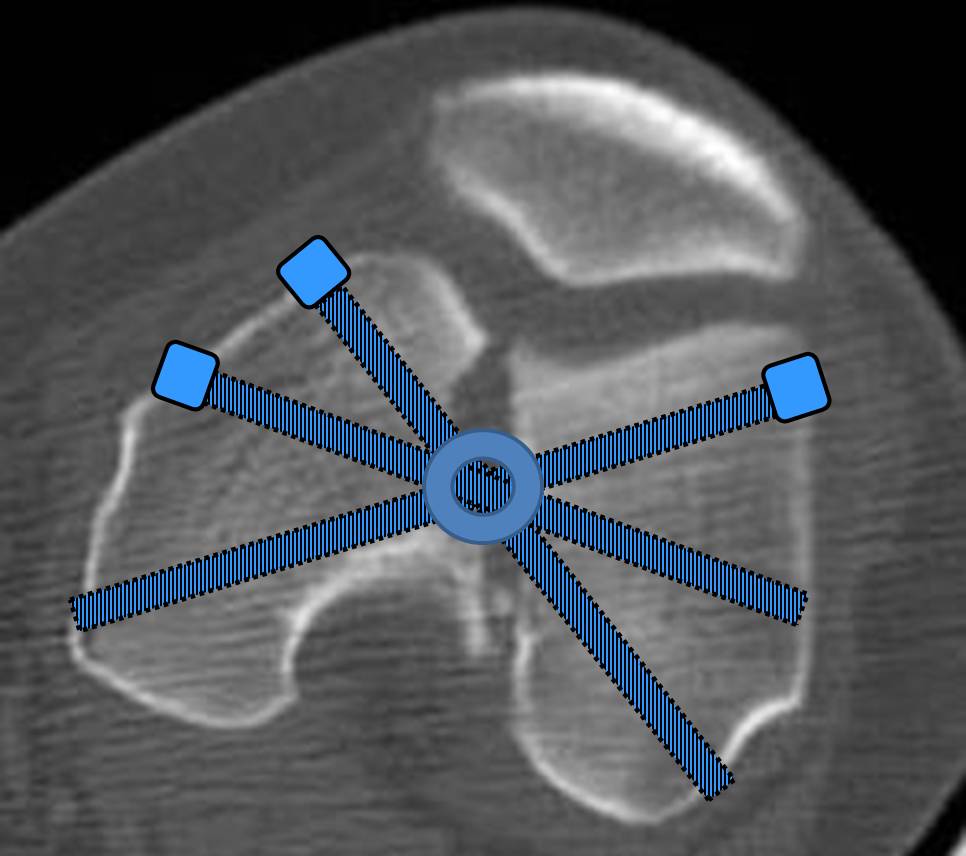

И уже лет шесть мы используем возможность ввести в дистальное овальное отверстие 3 винта, которые именно запираются в этом отверстии, не люфтят, а обеспечивают угловую стабильность - см картинку.

Получается и стабильно, и очень дистально, нижний край отверстия в 3 мм от дистального конца гвоздя.

С моей точки зрения, безусловная ценность предложенного Вами, Александр Николаевич, стержня состоит в возможности введения блокирующих винтов максимально близко к суставной поверхности дистального отломка, что значительно расширяет показания для применения интерлокинга. Можно предположить, что в техническом плане таким образом ввести блокирующие винты является непростой задачей. Кроме того, все они расположены в одной плоскости на небольшом расстоянии друг от друга.

Мне представляется, что конструкция с максимальными прочностными характеристиками будет иметь вид предложенной во вложенном файле. Такую конфигурацию расположения блокирующих отверстий на дистальном конце имеет стержень для большеберцовой кости фирмы ChM. Для бедренной кости такой стержень мне неизвестен. Поэтому в необходимых случаях (хорошо, что такие случаи встречаются не часто), как вариант, мы используем custom made стержень.